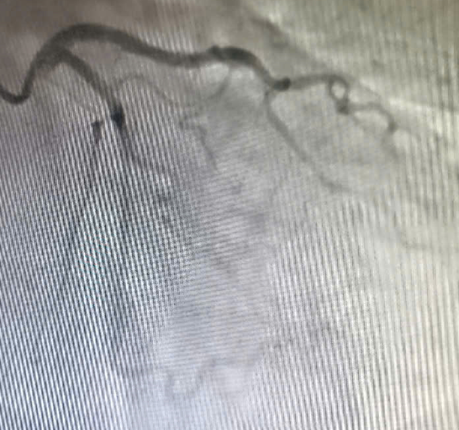

![]() |

| Hình ảnh hệ động mạch vành không thấy hẹp tắc - Ảnh BVCC |